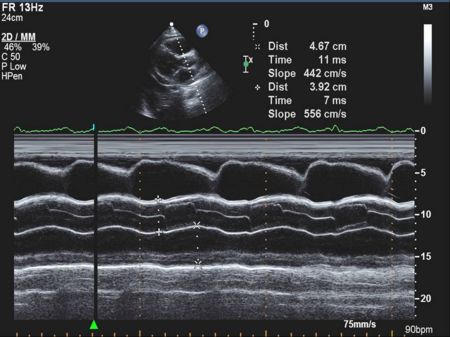

Mitral Valve M-mode Analysis

- Anterior leaflet with E/A appearance of diastology

- Decreased EF slope in MS

- Scalloping of leaflet tip in end systole in prolapse

M Mode in Mitral Stenosis

- Leaflet tips bright (calcified) and thickened

- E/F slope decreased